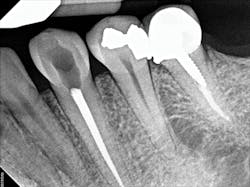

To determine whether tooth No. 21 or No. 22 was the issue, two periapical radiographs were taken. However, the results were inconclusive (figures 2–4). With clinical testing and 2-D radiographs providing no smoking gun, it was decided to use limited field-of-view CBCT (Carestream Dental CS 9000C 3D) on the region. CBCT revealed that tooth No. 22 was abscessed and a fair amount of the apical bone was completely gone (figures 5 and 6). In fact, since the time the pain began and when the patient presented at the practice, the tooth had abscessed at an alarming rate and was now considered an emergency situation.

Figure 2: A periapical radiograph showing a suspicious area (i.e., radiolucency) approximating the apex of tooth No. 20, as well as the defective distal occlusal restoration on tooth No. 21

Figure 3: A periapical radiograph showing tooth No. 22 with a radiolucency near the apex, which looked small relative to the areas on Nos. 20 and 21. There is also distortion of the appearance of the mental foramen in the area.

Figure 4: A periapical radiograph showing a partial view of the completed root canal therapy on tooth No. 22